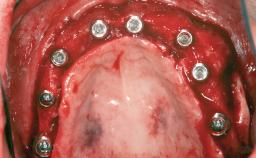

Iliac and Calvarial Bone Blocks for Onlay Grafting of a Severely Resorbed Edentulous Maxilla

# of Implants 8

Type of Implants Reduced-Diameter|Two-Piece

Bone Augmentation Horizontal|Sinus Floor Elevation|Staged|Vertical

Augmentation Materials Autogenous chips|Autogenous block(s)